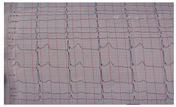

患者男,75岁,突发胸骨后剧烈疼痛4 h,于2014年2月12日5点30分入院。患者入院前4 h活动时突发胸骨后剧烈疼痛,伴大汗淋漓,持续不缓解,急来本院就诊。查体:T 36.2℃,P 70次/min,R 18次/min,BP 172/93 mmHg(1 mmHg=0.133 kPa),双肺未闻及干湿啰音。心界不大,心率70次/min,律齐,各瓣膜听诊区未闻及无杂音,无心包摩擦音。急查心电图示V2-V6 ST段抬高(图1),急查心肌酶轻度升高。拟诊"急性前壁心肌梗死",即行冠状动脉造影检查,造影结果显示:前降支远端转折处局限性轻度偏心性狭窄,内膜粗糙,前向血流正常。其余冠状动脉血管正常,前向血流正常。提示病变相关血管是前降支。考虑到冠状动脉病变与临床症状、心电图改变不符,多次复查心电图出现多个导联ST段持续抬高,心肌酶较前无明显变化,查D-二聚体正常。考虑到查体时心前区闻及心包摩擦音,且患者入院4 h后体温升至38.0 ℃,所以考虑感染因素引起"急性心包炎"的可能性大,查心脏超声提示少量心包积液,拟诊为"急性心包炎"。经抗生素抗感染、消炎止痛药物等对症治疗9 d后,仍有胸痛,遂进一步行胸部X线片检查示:两肺纹理增多,主动脉型心影。复查心脏超声示,升主动脉略扩张(升主动脉径32 mm),左室舒张功能减低,少量心包积液。鉴于升主动脉增宽、胸痛仍未缓解,心电图ST段持续抬高,遂考虑"主动脉夹层"的可能,给予主动脉CT造影结果示胸主动脉自升主动脉开口处至左侧髂总动脉近段及头臂干及左颈总动脉近段见双腔改变,假腔呈环形围绕真腔,心包腔内见液性密度。诊断为:主动脉夹层(Stanford B型)。患者于2月21日在全麻下,穿刺左桡动脉置入6F桡动脉鞘管,沿标测导管以18 mL/s,30 mL,600 kpa压力造影显示,左锁骨下动脉远端起为弥漫性血管夹层,破口即在此处,作好标记,在加长加硬专用导丝指引下,采用覆膜支架输送系统植入MicroPort Hercules 3.6 cm×14 cm带膜支架,准确定位后释放,重复造影支架位置良好,破口完全覆盖,血管造影结果满意。术后治疗观察9 d,症状完全缓解,给予出院。随访半年,患者病情稳定。